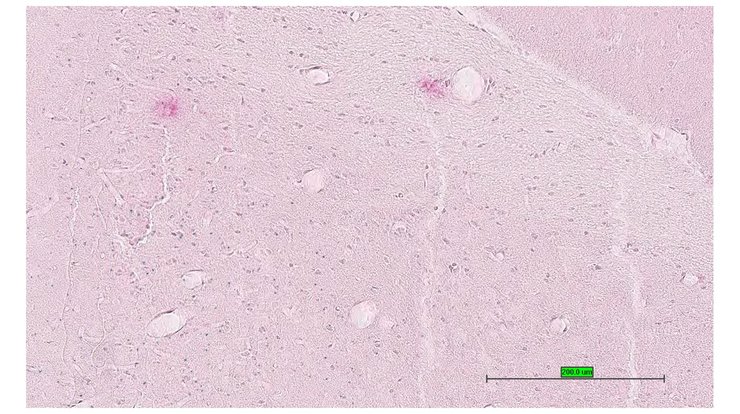

TS28: olfactory lobe Present UC Davis_1877355